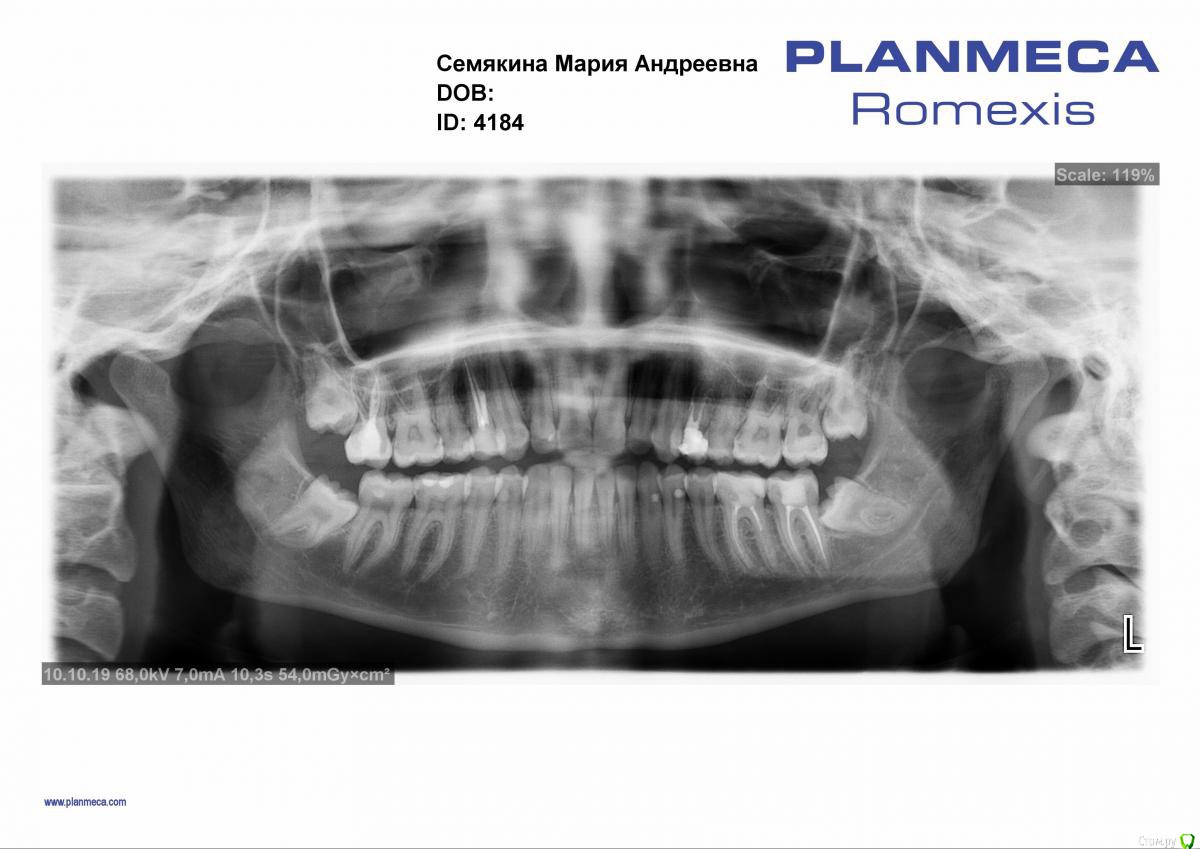

Marialalala Опубликовано 10 октября, 2019 Поделиться Опубликовано 10 октября, 2019 Доброго времени суток! Планирую беременность, сделала панорамный снимок (прикрепляю) и ужаснулась, особенно "омерзительными восьмерками", подскажите, какой обязательный план действий мне необходим ДО беременности, а что можно отложить. Спасибо! Ссылка на комментарий

St. Опубликовано 10 октября, 2019 Поделиться Опубликовано 10 октября, 2019 Добрый день. 8 обязательно удалить, особенно нижние, они очень коварно упираются в соседей. И посмотреть промежутки между верхними 6 5 справа и слева, между 6 и 7 внизу справа на предмет скрытого кариеса Ссылка на комментарий